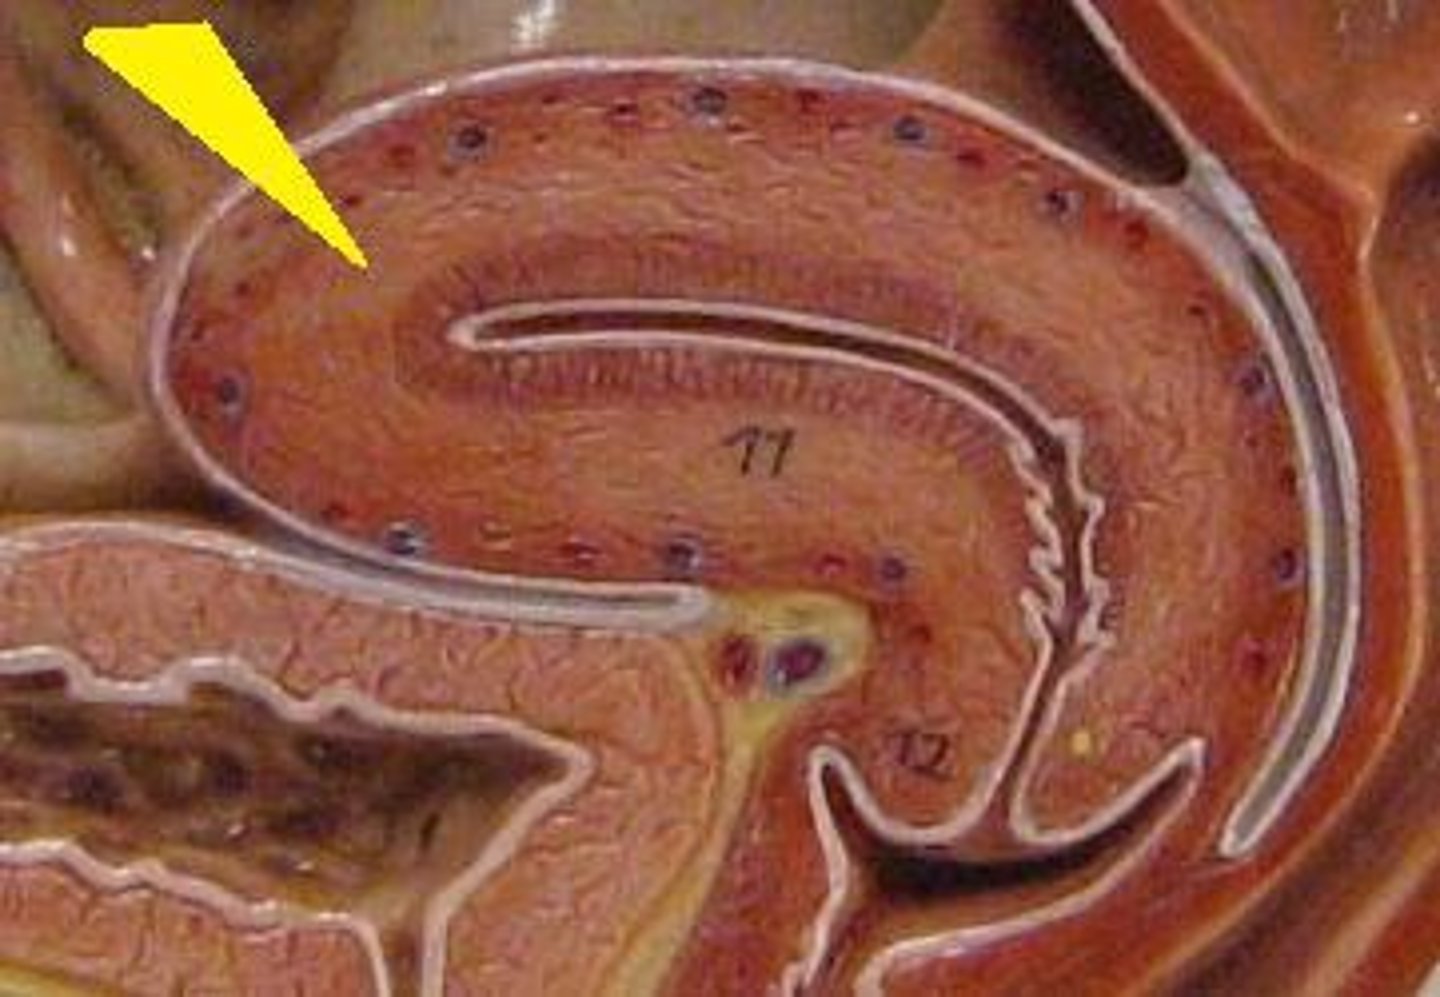

corpus luteum

8

early corpus luteum

9

late corpus luteum

10

corpus albicans

11

granulosa cells

12

theca cells

13

antrum

14

ovary

1